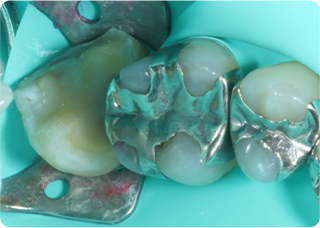

セラミックアンレー症例②

術前

むし歯除去&IDS

ラバーダム防湿

術後

| 主訴 | 右下奥歯の銀歯を白くしたい |

|---|---|

| 治療期間/回数 | 2週間、2回 |

| 価格(税込) | 143,000円(税込) |

| リスク・副作用 | セラミックの破損、一時的な知覚過敏が生じる場合がある |

| ポイント | 銀歯の中はむし歯になっていた。金属イオンにより歯の内部に黒い部分があるが、むし歯を染め出すう蝕検知液を使用し、選択的にむし歯のみを除去。また、セラミック装着時にラバーダム防湿を行うことで、詰め物の接着効果を最大限発揮できるようにした。 |